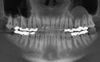

methamphetamine-related dental caries